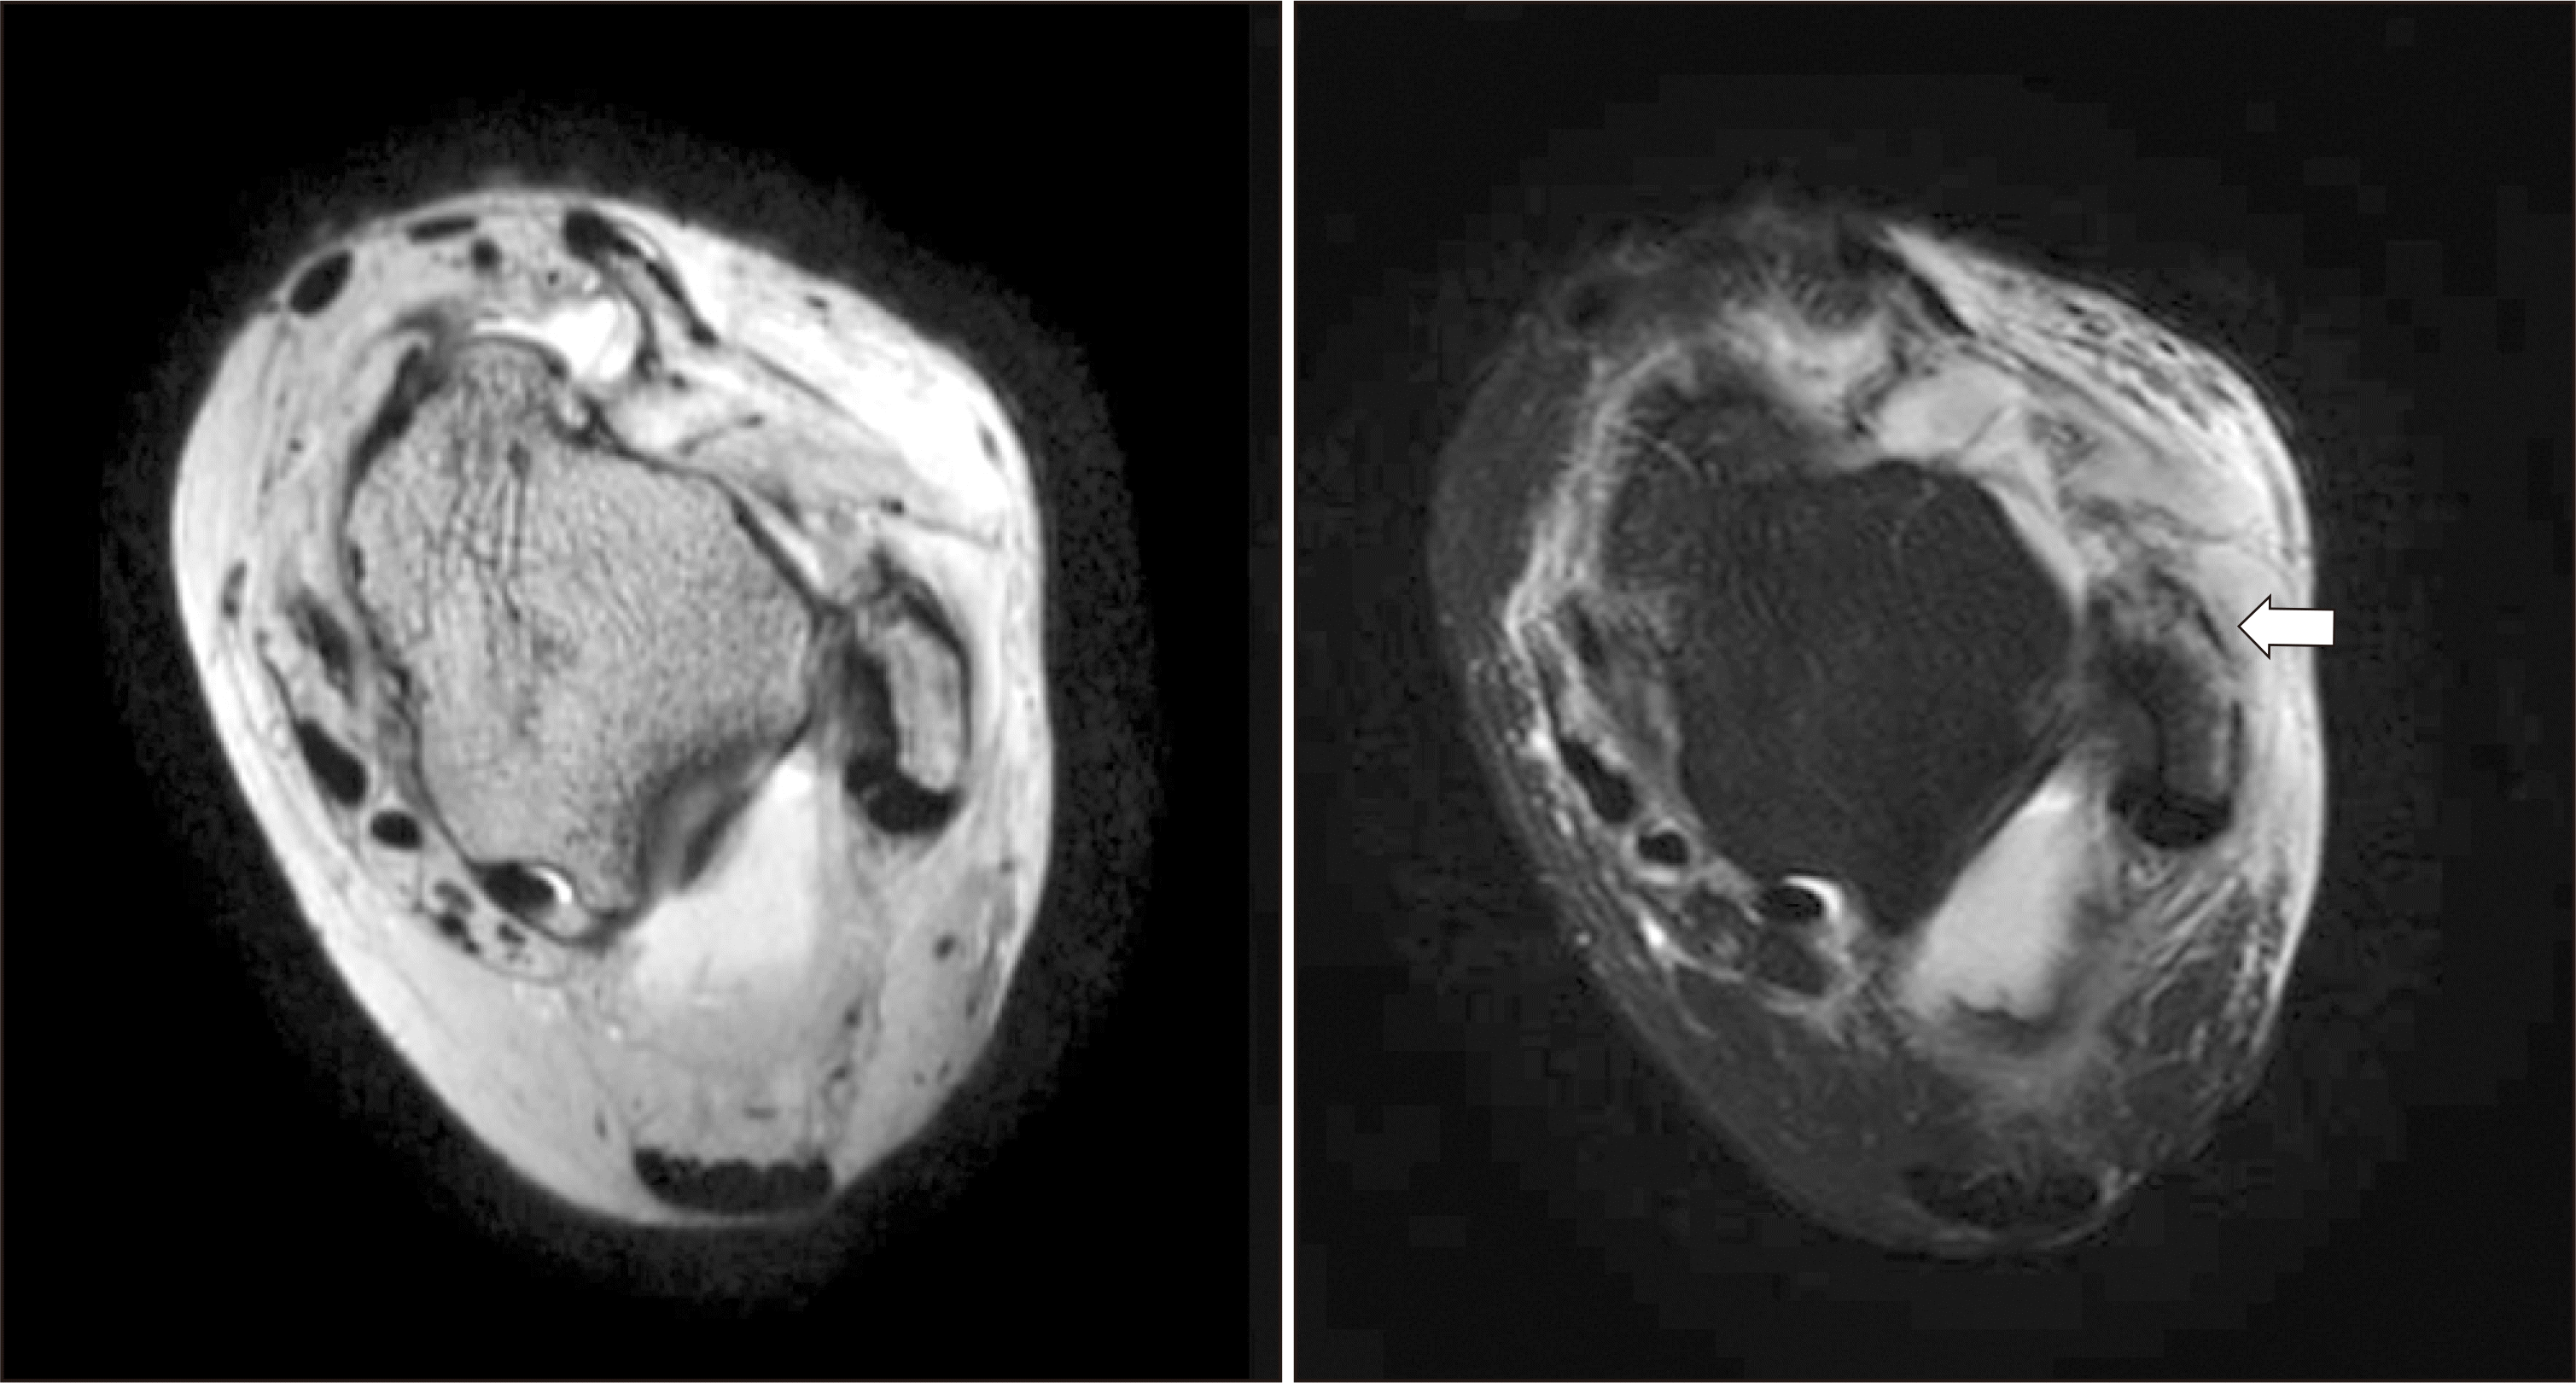

Figure 2

Magnetic resonance imaging of the left ankle. T1- and T2-weighted image show anterior talofibular ligament tear with an avulsion fracture of the lateral malleolus (arrow) in the left ankle.